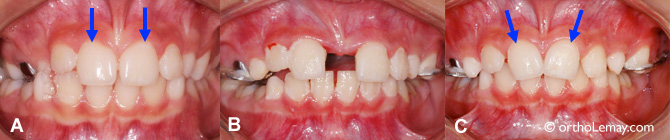

(A) Occlusion croisée postérieure bilatérale (flèches) causée par une constriction maxillaire chez une fille de 11.9 ans. Les incisives centrales supérieures sont relativement parallèles l’une à l’autre.

(B) Après 4 semaines d’activation de l’appareil d’expansion rapide, les incisives centrales sont de niveaux différents et commencent à s’incliner vers le centre.

(C) Une semaine plus tard, lors de l’immobilisation de l’expansion, les incisives centrales semblent se redresser légèrement.

(D) 2 ans après l’expansion, les dents permanentes sont toutes sorties, mais les incisives centrales sont encore inclinées même si elles se sont rapprochées quelques semaines après la fin de l’expansion. Une seconde étape de traitement corrigera ces malpositions dentaires.